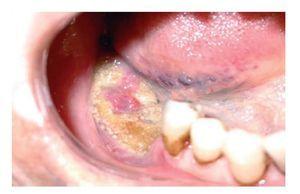

— Estadio I: hueso necrótico expuesto en pacientes que son asintomáticos y sin infección clínica (fig. 2).

Figura 2 Hueso necrótico expuesto en paciente asintomático y sin infección clínica. Fuente: http://www.scielo.d/fbpe/img/rmc/v134n9/fig11¿02.jpg